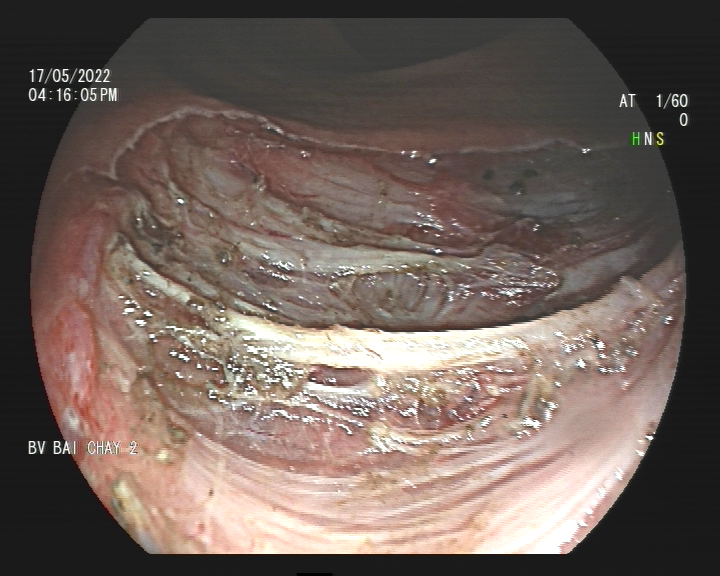

Sau 90 phút thực hiện thủ thuật, polyp lớn ở trực tràng được cắt hoàn toàn, không xảy ra các tai biến hay biến chứng do thủ thuật. Sau 1 ngày điều trị tại khoa Nội tiêu hóa, sức khỏe bà T. đã ổn định.

Hình ảnh polyp ở trực tràng được cắt hoàn toàn